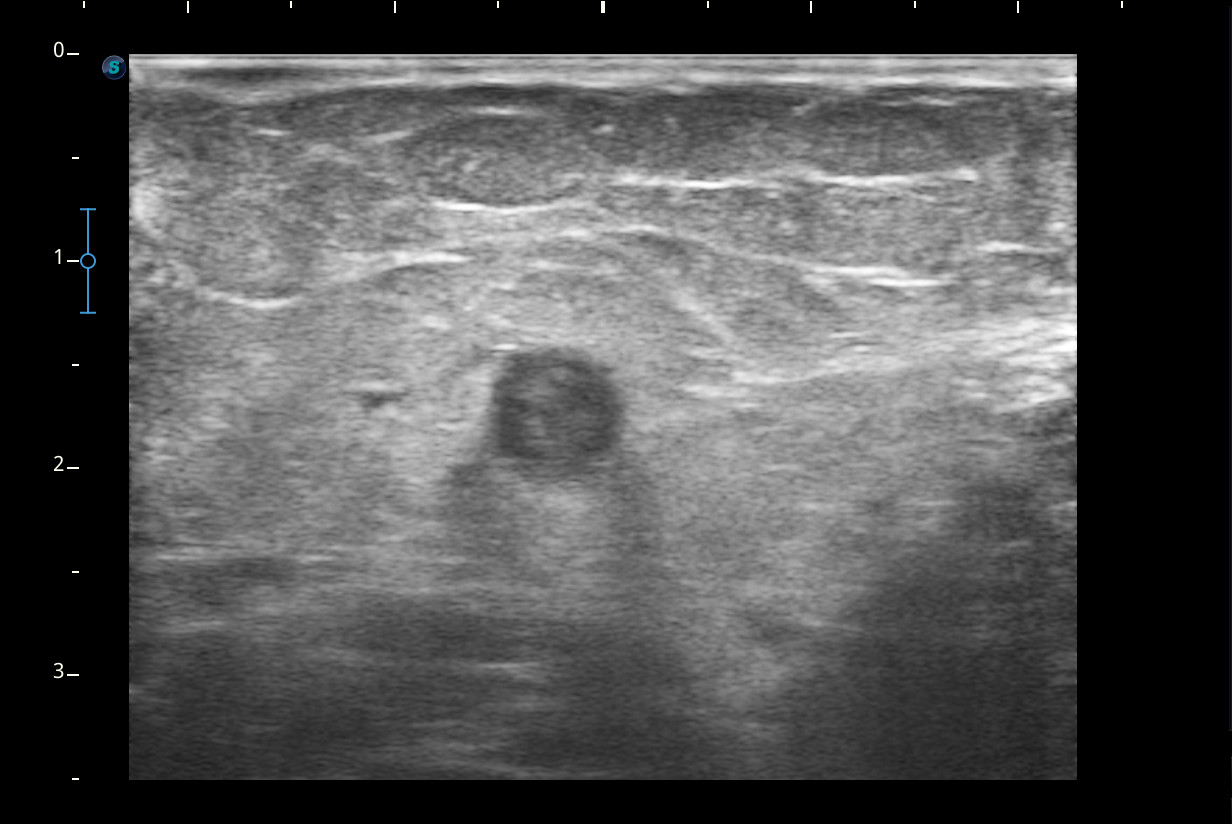

Hallazgos ecográficos

Se visualiza congestión del tejido subcutáneo del brazo y ocupación de la luz de la vena basílica del brazo por un trombo.